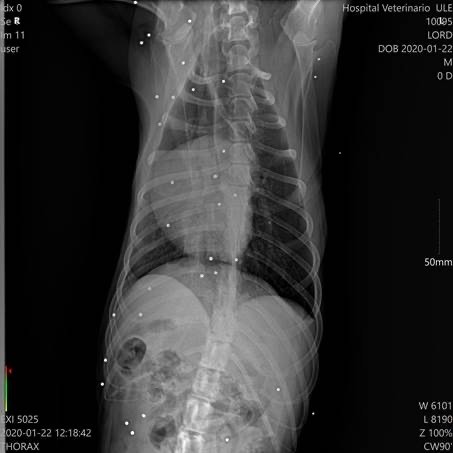

Der kleine Kerl begann zu humpeln und nach weiteren Untersuchungen sowie dem Besuch bei einem Spezialisten, wurde festgestellt, dass er unzählige Schrotkugeln im Körper hat und Arthrose in diversen Gelenken.Lord wird leider zukünftig auf Schmerzmedikamente angewiesen sein.

Der kleine Kerl begann zu humpeln und nach weiteren Untersuchungen sowie dem Besuch bei einem Spezialisten, wurde festgestellt, dass er unzählige Schrotkugeln im Körper hat und Arthrose in diversen Gelenken.